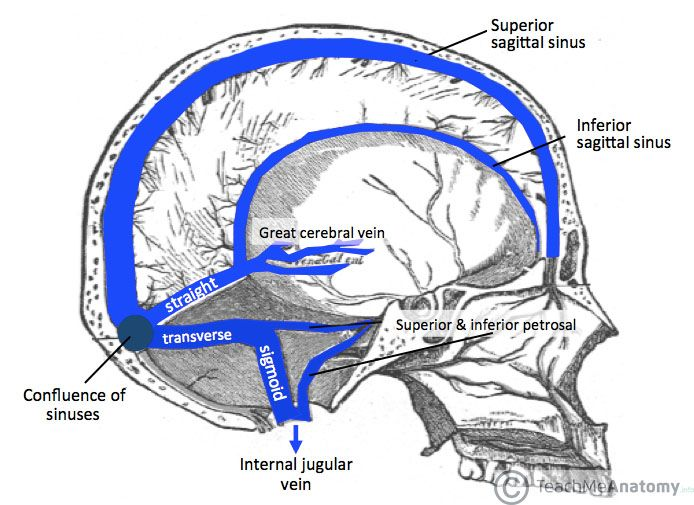

顱內